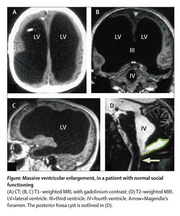

Французский чиновник 44 лет, отец двух детей, пришёл в клинику пожаловаться на боли в ноге.

Слово за слово, ему сделали компьютерную томографию мозга, потом ЯМР (он же MRI).

Оказалось, что у него практически нет мозгов.